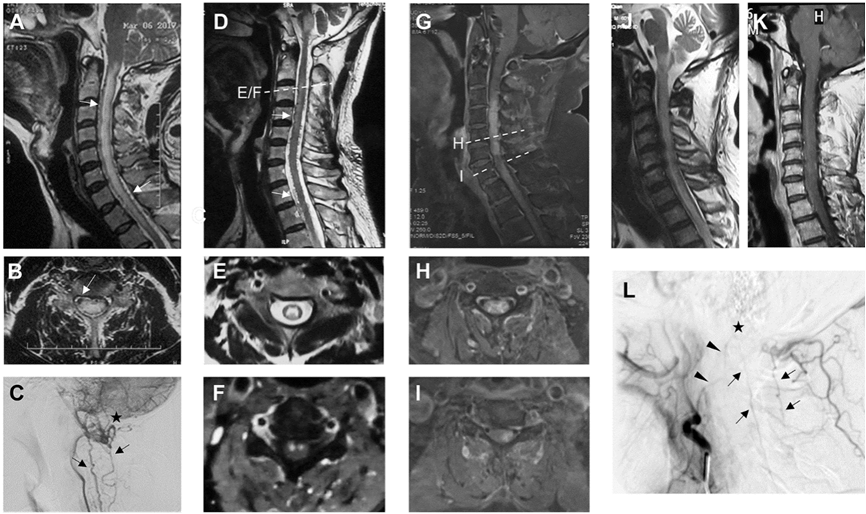

Figure 2. Representative imaging of CCJVHM patients

All nine recurrent patients (13.8%) had dural arteriovenous fistulas, corresponding to the two recurrence patterns shown in Figure 5. The first one was revascularization (Figure 5A-L). A total of eight patients underwent transarterial embolization at the time of first treatment. five patients used Onyx as embolic material, and three patients underwent reoperation for embolic recanalization. The recurrence rate was higher in the embolization group than in the surgical group (Table 3, p=0.007). Kaplan-Meier analysis showed an 11-fold increased risk of recurrence in the embolization group (median time to recurrence=34 months, p<0.0001, Figure 6A). Another pattern of recurrence was a de novo contralateral supplying arteriovenous fistula. Four patients (3 with surgery and 1 with embolization) had this type of recurrence, and their draining veins could be the same (Figure 5O/S, n=3) or different (Figure 5I/J, n=1) from the first disease. The remaining patients with recurrence (1 surgery, 2 embolization) could not be accurately determined the cause because of the lack of first imaging data. Most of the recurrent patients (8/9, 88.9%) underwent secondary treatment with microsurgery at our institution.